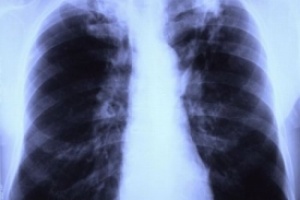

Зачестяват случаите на туберкулоза у нас

65 са новодиагностицираните с туберкулоза в страната само за седмица. Данните са от кампанията на Министерството на здравеопазването Седмица на отворените врати.

3144 души се възползваха от безплатните прегледи и консултации за туберкулоза по време на кампанията.

Безплатните прегледи се проведоха от 12–16 септември в специализираните лечебни заведения във всички 28 области в страната. По време на кампанията 65 души бяха диагностицирани със заболяването и приети за лечение, а при 184 се откри латентна туберкулозна инфекция. Тези хора са насочени за химиопрофилактика. През Седмицата на отворените врати 4826 пациенти се подложиха и на скрининг за риск от развитието на туберкулоза чрез попълване на анкетна карта.

Регулярното провеждане на седмици на отворените врати съдейства за навременната диагностика, лечение и профилактика на туберкулозата. Затова през декември МЗ и Програма „Подобряване на контрола на туберкулозата в България“ ще проведат още една седмица на отворените врати.